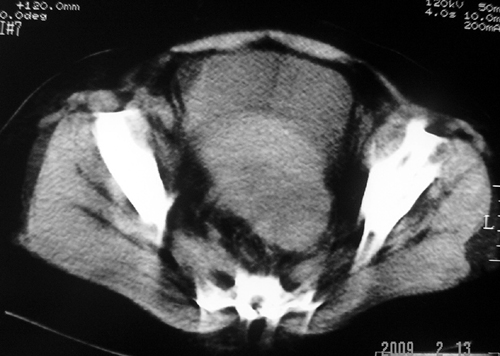

以下是引用余辉在2009-2-14 8:37:00的发言:[br]宫颈左后壁见较大低密度肿物影且向左后上方突出,宫腔内见大片状低密度区,考虑宫颈肿瘤,宫颈癌可能性大,伴宫腔积液或转移